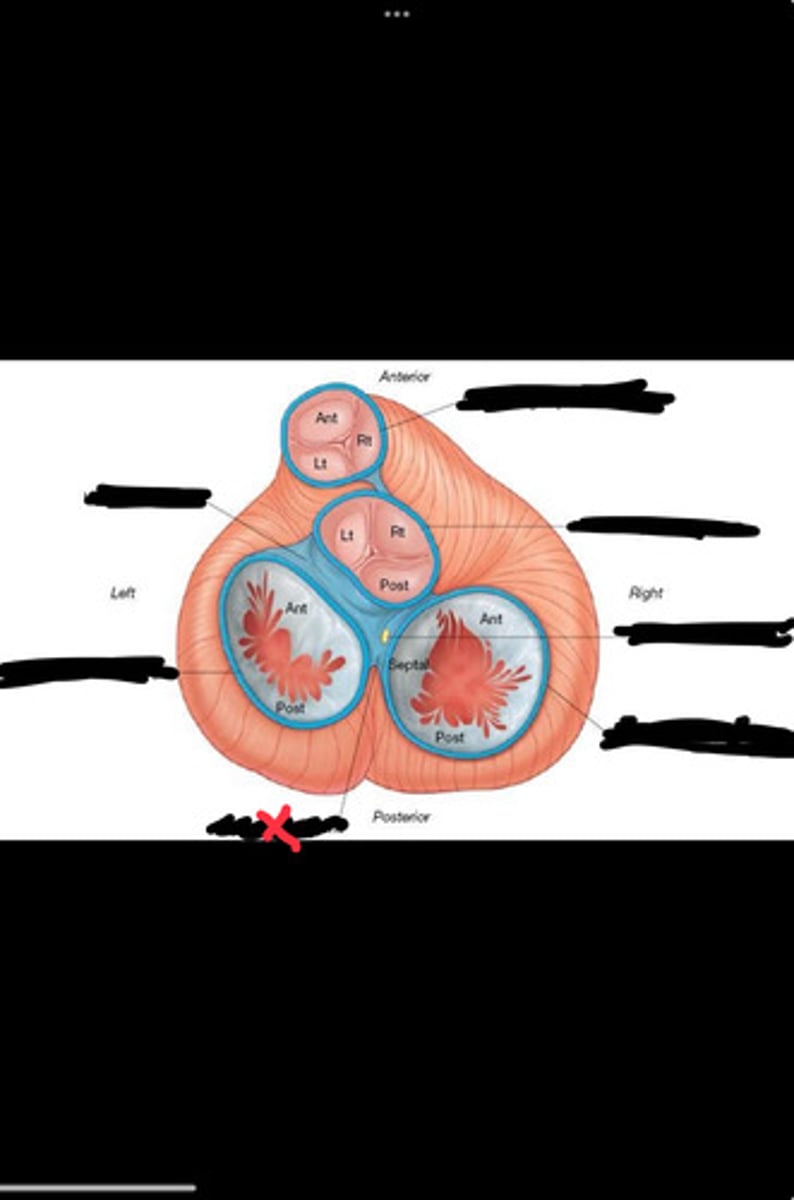

Right fibrous trigone

Left fibrous trigone

Fibrous ring of pulmonary valve

Fibrous ring of aortic valve

Atrioventricular bundle

Right atrioventricular ring

Left atrioventricular ring